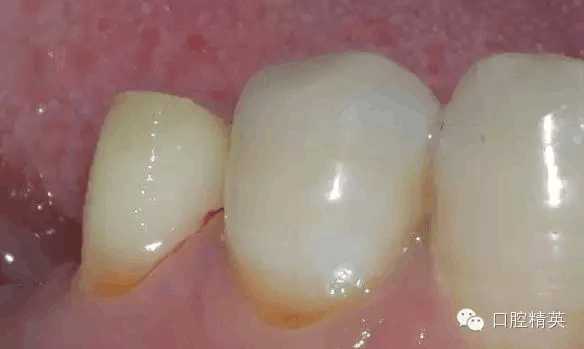

鄰面制備完成后

修整后